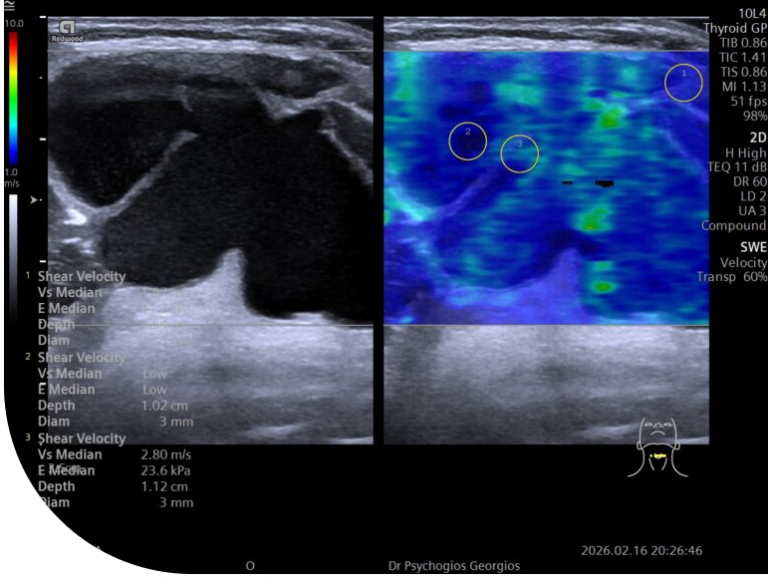

Ελαστογραφική υπερηχογραφική απεικόνιση κύστης θυρεογλωσσικού πόρου με εσωτερικά διαφράγματα.